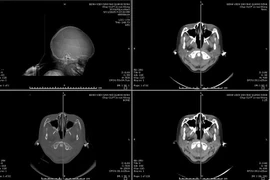

Tai nạn tại nhà, trẻ 6 tuổi ngừng tim, chấn thương sọ não nặng

Sau ca mổ mở nắp sọ, lấy máu tụ, bé N.M.N đã tỉnh táo, ổn định sức khỏe và được ra viện sau 2 tuần điều trị tích cực tại Quảng Ninh.